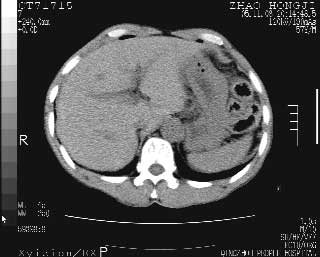

临床资料:男性,57岁,上腹部疼痛并5天,突然加重并延及全腹伴恶心5小时入院。胰淀粉酶化验在正常范围。检查:腹肌紧张,全腹压痛、反跳痛,尤以右上腹部为著。肠鸣音减低。血常规:wbc14.6x10/9, n:11.3x10/9 ,血压:135/90mmhg. 胸部透视:腹部肠腔轻度张气,未见其它异常改变。

肝右前缘少量积气,其他未见明显异常.考虑上消化道穿孔.

小网膜囊积气液,胃壁僵硬。考虑胃穿孔。

小膜网膜积液,肝缘气腹征,上消化道穿孔。

肝缘见少许气体,胰尾部见少许气体包饶(蓝色圈),12指肠上部或球部邻近胆囊周边也可见少许气体影(黄色圈),并忖托出胆囊壁,12指肠远段肠道内未见明显气体(白色箭)。

肝脏前缘见少量积气、胰尾部见少许气体包饶,肾前筋膜未见增厚,临床淀粉酶不高,意见:上消化道穿孔。

入院3小时后行剖腹探查术,见腹腔内大量脓性混浊液约1000ml,十二指肠球部溃疡穿孔,溃疡面约2.5x2cm,穿孔直径约0.6cm。胃内容物外益,周围组织炎性水肿明显。行十二指肠穿孔修补术。术后诊断:

1、十二指肠溃疡穿孔

2、弥漫性腹膜炎

对于少量的腹腔游离气体,ct检查较普通透视有绝对的优势,它不仅可以看到肝脏前上缘的气体,而且还能够看到小网膜区的游离气体。从而可以肯定诊断。各位分析战友的很好,感谢大家的参入!